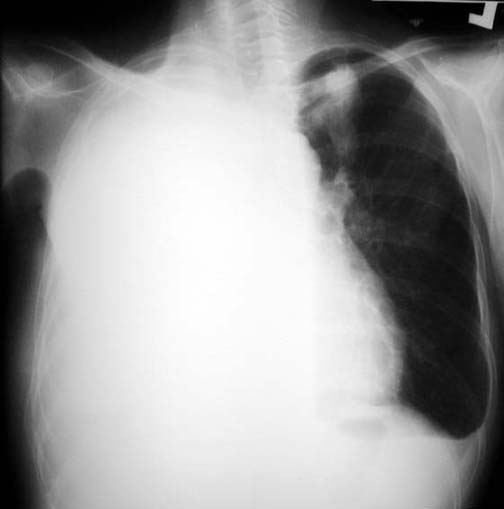

Massive Pleural Effusion

• Unilateral homogenous density

• Loss of diaphragmatic and right sided cardiac silhouettes

• No mediastinal shift

• Blunting of left cardiophrenic angle

• LUL gloved finger density. Sorry I do not remember the etiology for this case.